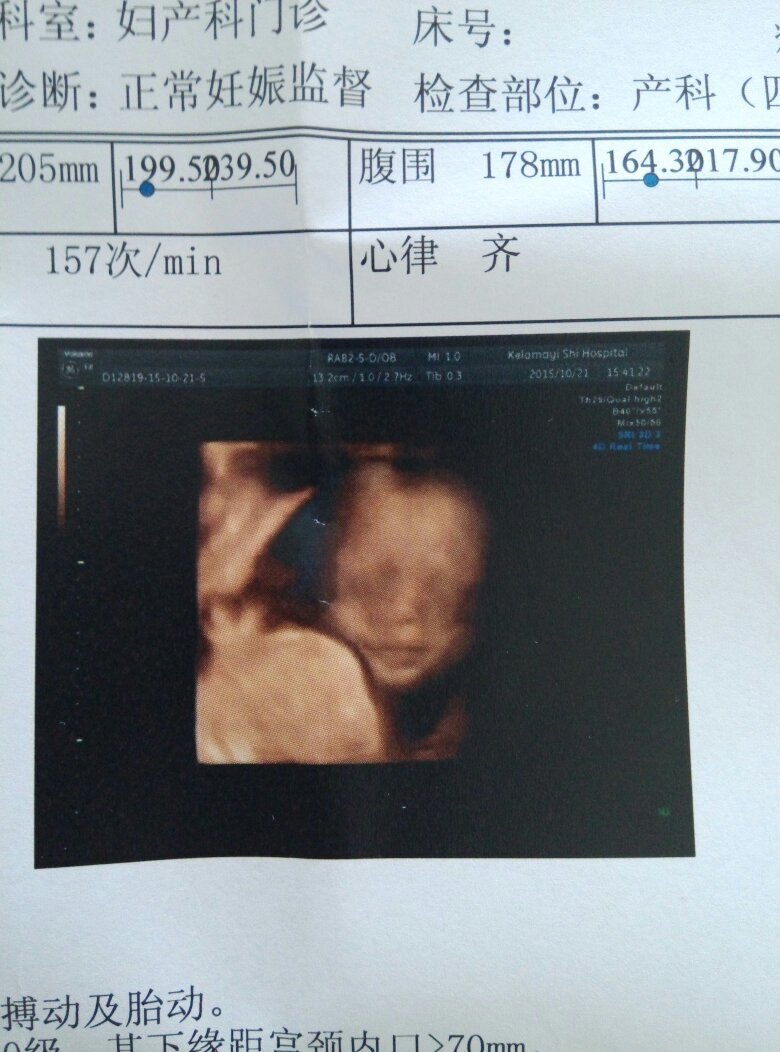

女,25岁。请专家帮我看看宝宝有没有兔唇,坐四维的时候医生什么都没有说,但是看图像感觉上唇有阴影,很担心

宝妈你就放心吧!这不是兔唇,怀孕期间,越金蒸肆是都最后阶段,就会越胡思敢肿乱想,人的正常心理,裁碗没事的请放心待产吧!祝你跟宝宝平安